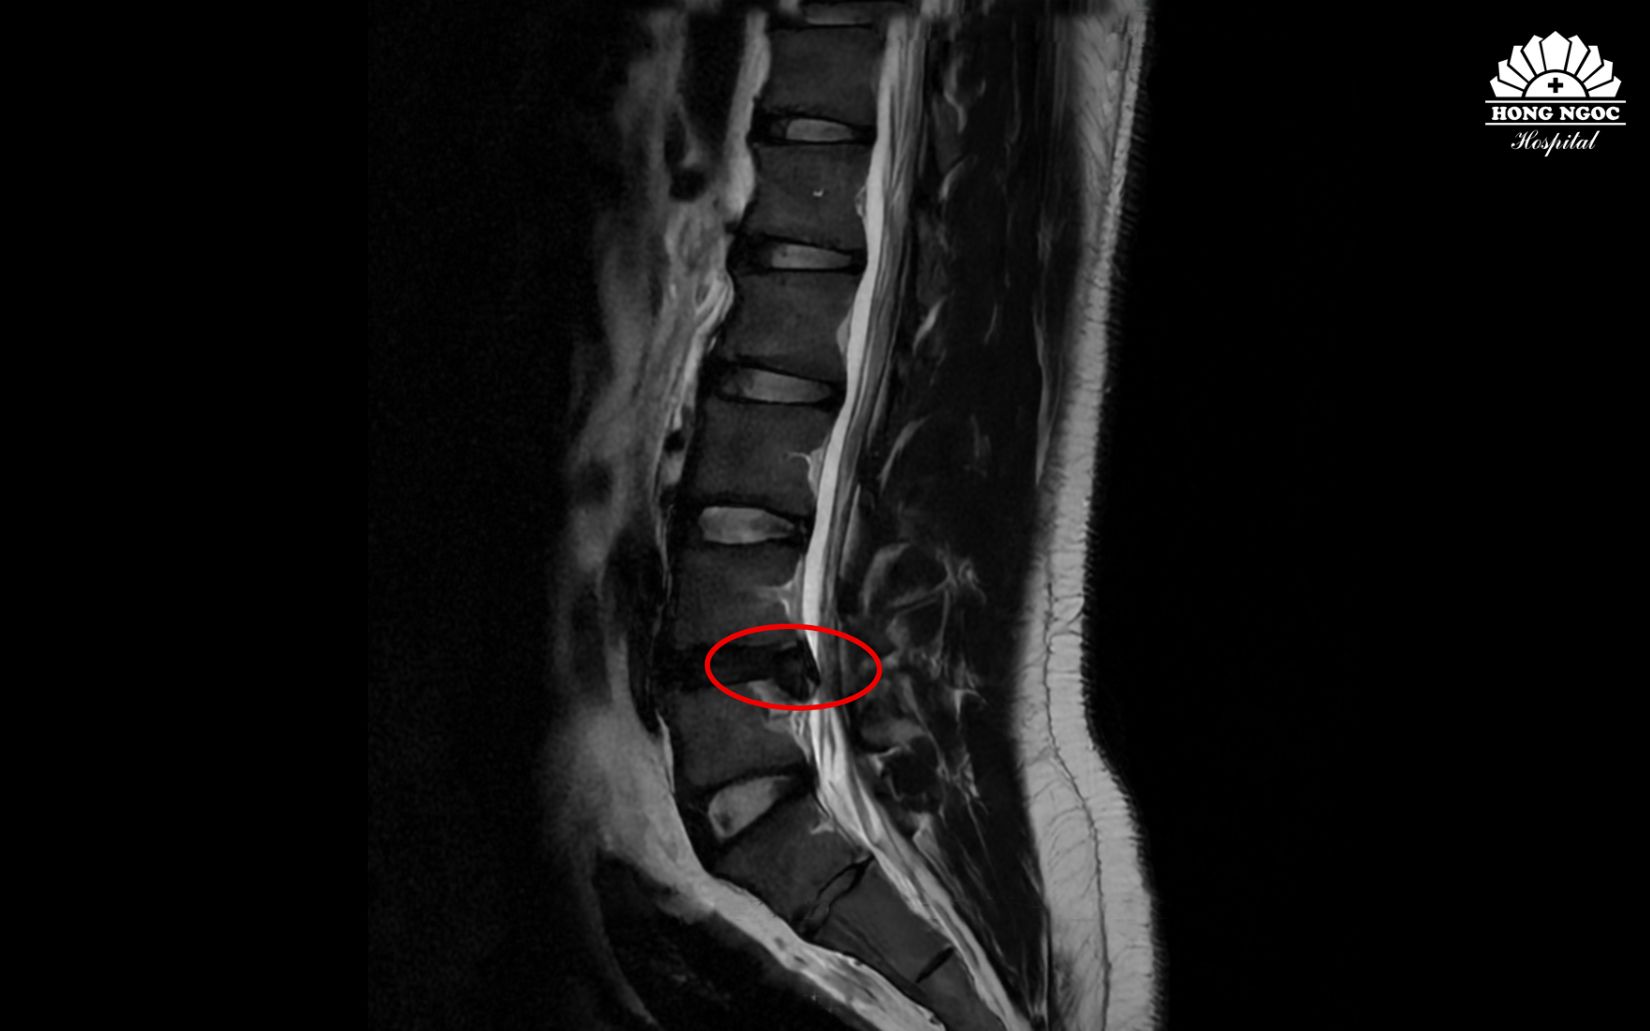

Qua thăm khám và kết quả chụp cộng hưởng từ (MRI), bệnh nhân được chẩn đoán thoát vị đĩa đệm cột sống thắt lưng L4/L5 gây chèn ép rễ thần kinh, cần phẫu thuật để tránh biến chứng liệt.

Hình ảnh thoát vị đĩa đệm cột sống L4/L5 qua phim chụp